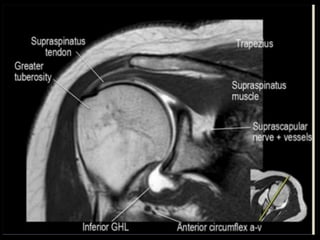

Shoulder

Joint.